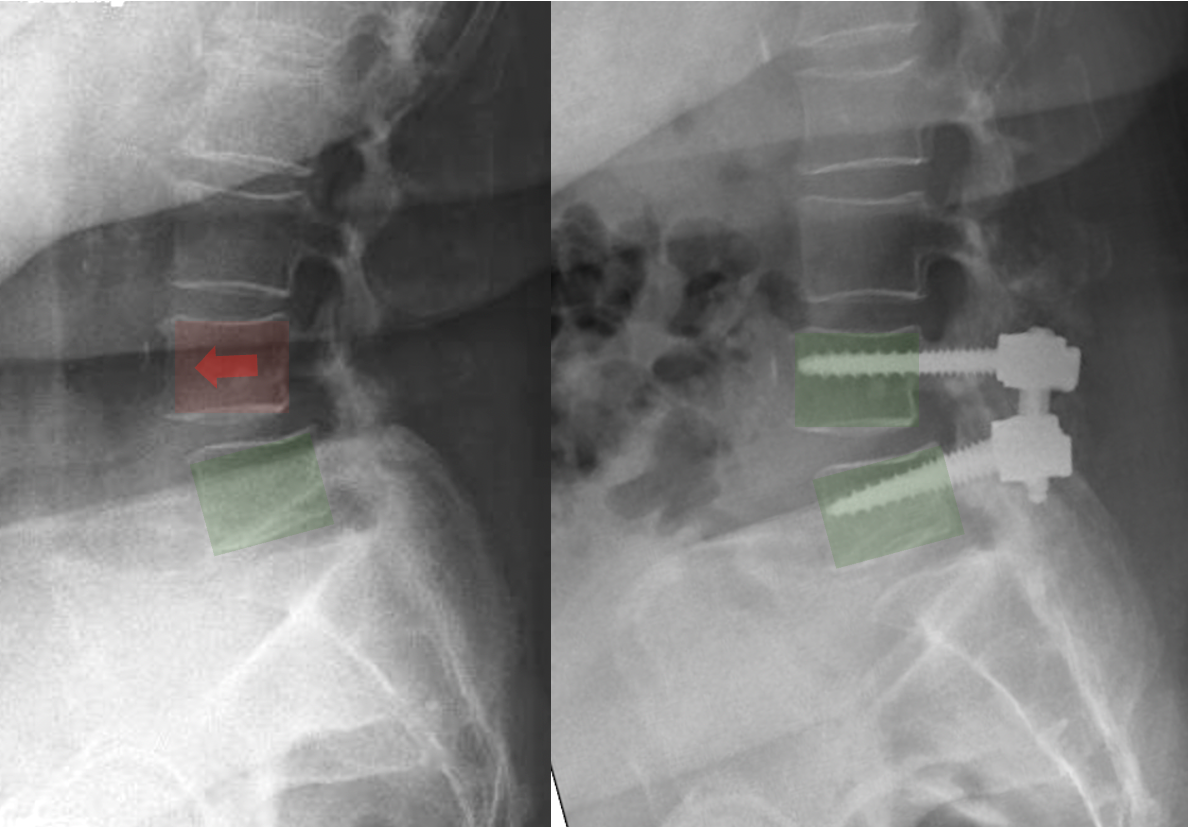

X-ray of cervical spine showing the placement of artificial disc implants with screws and a highlighted red area indicating a problem.

How Is the Surgery Performed?

During posterior lumbar decompression and fusion:

• An incision is made in the lower back

• Muscles are gently moved aside

• Pressure on the spinal nerves is relieved

• Screws and rods are placed into the vertebrae

• Bone graft is placed to allow the vertebrae to fuse together

Over time, the bone graft heals and the vertebrae grow together into a single solid bone.